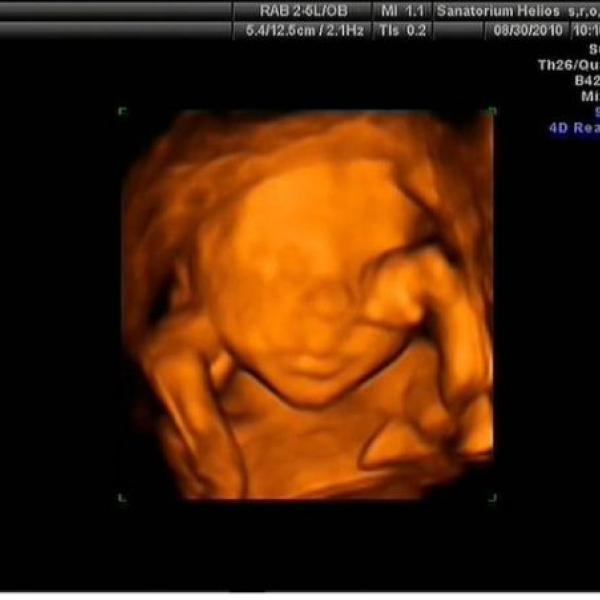

Ahoj spolutěhulinky :) tak jsem konečně taky vyfotila domeček našeho Tobíka :h: je to focené před týdnem v 30tt a už teď mi přijde, že mám pupík zase větší :00: Večer už mi vad